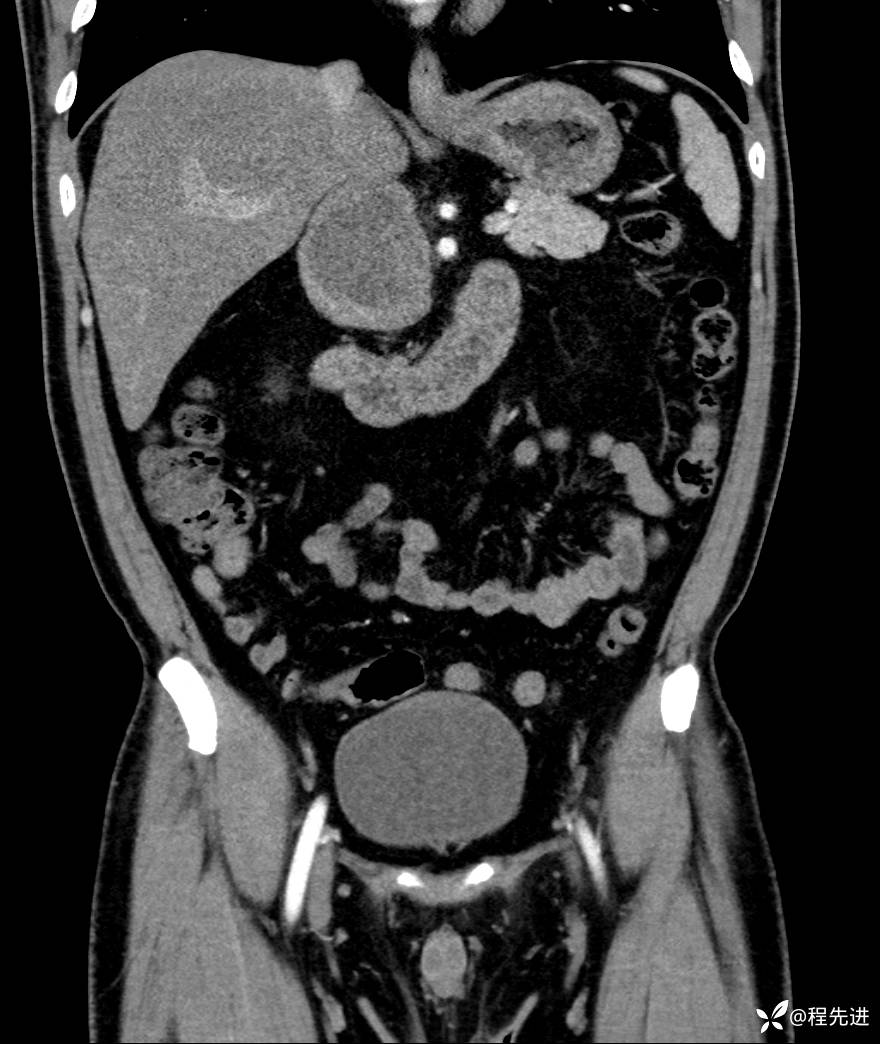

【腹盆】特别精彩病例|发现腹膜后肿物1月余

主诉:发现腹膜后肿物1月余

现病史:患者1月余前查体,行超声检查提示:后腹膜囊实性肿块;慢性胆囊炎伴胆囊内结石;无腹痛腹胀,不伴腹泻发热等;偶感腰背部酸痛。

CT平扫+增强: